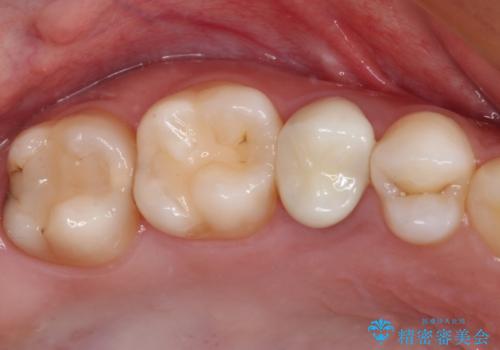

その後骨形成処置を行い、治癒を待って補綴治療を行うこととしました。

かなり深い位置にまで虫歯が及んでいたため、かなりの量を引っ張り出す必要があり、残された歯根は短く小さい状態となりました。

今後も定期的にレントゲンを撮るなど、経過を追っていく必要があります。